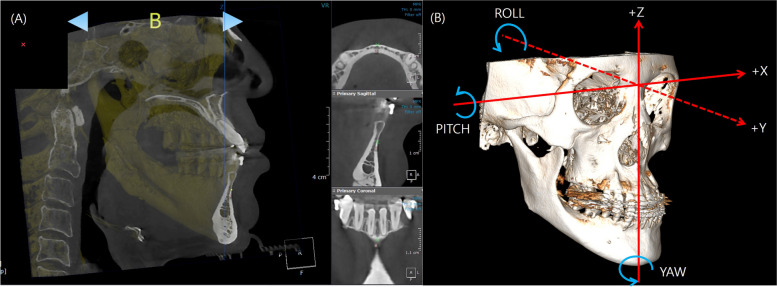

Methods: This retrospective cohort study investigated patients who underwent mandibular setback surgery using bilateral sagittal split ramus osteotomy. Three-dimensional CT scans were taken at three different time points. Evaluation of the postoperative stability involved measuring changes in the x, y, and z axes as well as roll and yaw rotations of the mandible at specific landmarks (B point, mental foramen) on 3D CT scans obtained immediately after surgery and 6-12 months postoperatively. They were categorized into four groups based on bilateral mandibular height asymmetry through Asymmetry index (AI). The one-way ANOVA was implemented to compare the intergroup differences and Tukey's post hoc test was employed. Additionally, the Pearson correlation coefficient was also calculated.